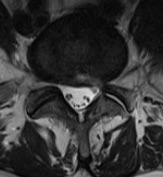

手術後のMRI画像 脱出した椎間板ヘルニアは全摘出され、神経の圧迫が解除された。強い左脚の痛みは手術直後から消失し翌日に自宅退院できた。